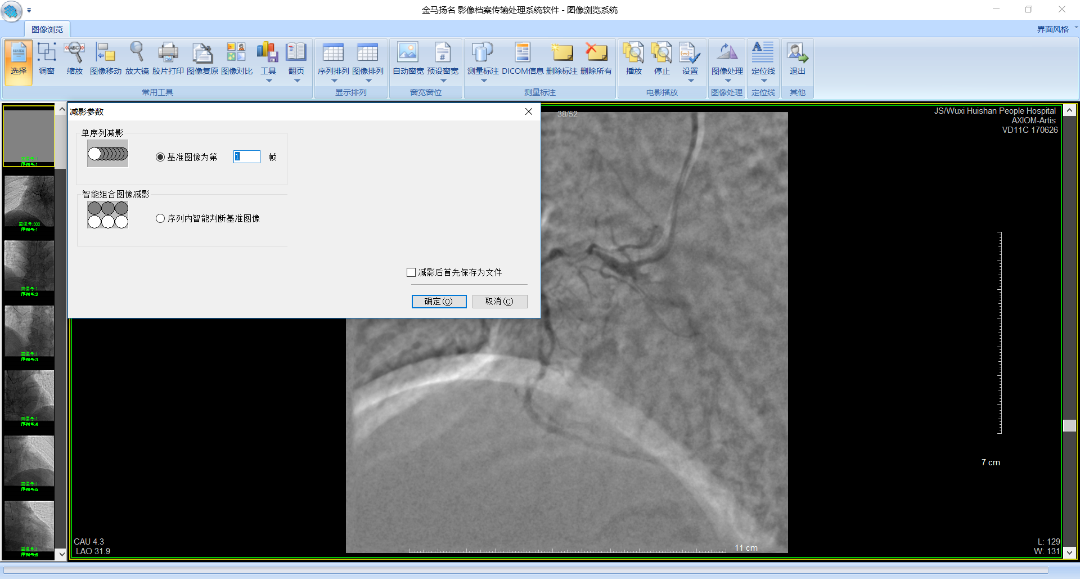

• DSA剪影功能(选配)

图片